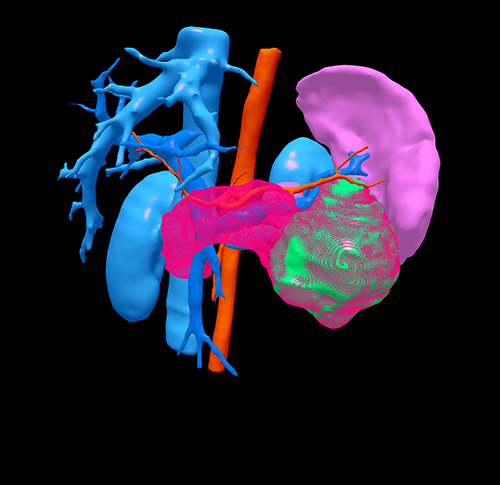

胰体尾实性假乳头状瘤---腹腔镜胰体脾切除